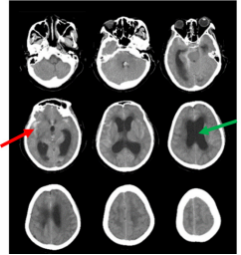

颅脑CT:蛛网膜下腔出血(红色箭头),脑室扩大(绿色箭头)

然而在开颅手术治疗后4月,能独立行走,生活自理的她,突然变得需要在家人搀扶下,才能勉强下地行走,反应变得稍微迟钝,对近期事情记忆困难,无法做简单的计算题,甚至出现了大小便失禁。家人将其再次送诊我院,先后行颅脑CT及MRI,提示“脑室较前明显扩大,脑室周围渗出明显”,证实了“颅内出血后脑积水”形成,并明确其正在缓慢进展中,完善“腰穿脑脊液释放试验”后,又能下地行走,提示了“脑脊液引流治疗,对患者治疗有效”,